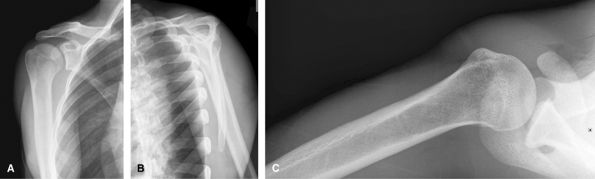

Trauma, Acute Injuries

To evaluate for humeral neck/tuberosity fractures and

shoulder dislocations. CT is useful to assess for Hill Sachs lesions and

bony Bankart. MRI can be difficult to interpret acutely due to blood

tracking into the rotator cuff from tuberosity fractures. Subacutely,

MRI may be useful to assess for accompanying internal derangement.

![]() |

Figure 14 (A) AP scapula,- neutral rotation. (B) Lateral “Y” view. (C) Axillary view, as tolerated by patient.